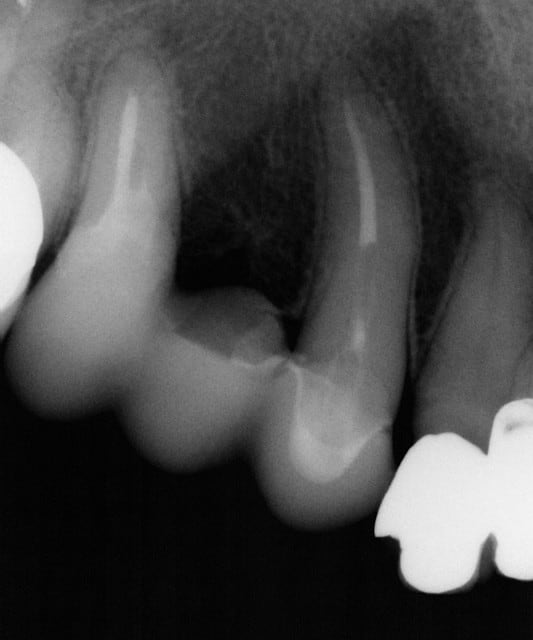

Voici les photos du premier cas, les embrasures ont été renforcées au maximum car la DV est très réduite, j'ai préféré l'option endocouronne sur la 15 qui semblait présenter plus de surface de collage qu'une reconstitution classique à ancrage avec tenon fibré, après test en résine d'un bridge provisoire.

Effectivement je reconnais parfaitement que l'esthétique pourrait être améliorée...

Comme je l'ai dit, il s'agit de mon premier bridge en emax et l'articulé n'etait pas très favorable, ce qui m'a conduit à préférer donner la priorité à la solidité au dépend de l'esthétique car je ne voulais prendre aucun risque, quitte à exagérer volontairement les connexions, à la grande satisfaction de ma patiente âgée et arthritique qui désirait des séances courtes et sans position allongée.

Il est tout à fait possible d'accentuer les caractères anatomiques en augmentant la précision de l'outil de réglage biogénérique et obtenir des sillons plus fouillés avec des pentes cuspidiennes plus marquées ainsi que de galber et ouvrir les embrasures mais en diminuant en même temps l'épaisseur de la céramique...

J'ai aussi du reprendre totalement la forme et les dimensions de ce bridge en gonflant le tiers occlusal car la proposition du système n'était pas adaptée car trop réduite et anarchique , ce qui ne fut pas le cas de mon 2° bridge.

l ne s'agit pas ici d'un concours de beauté mais de la faisabilité de la réalisation d'un bridge avec la version 4.03, ce qui est de toute évidence tout à fait possible.